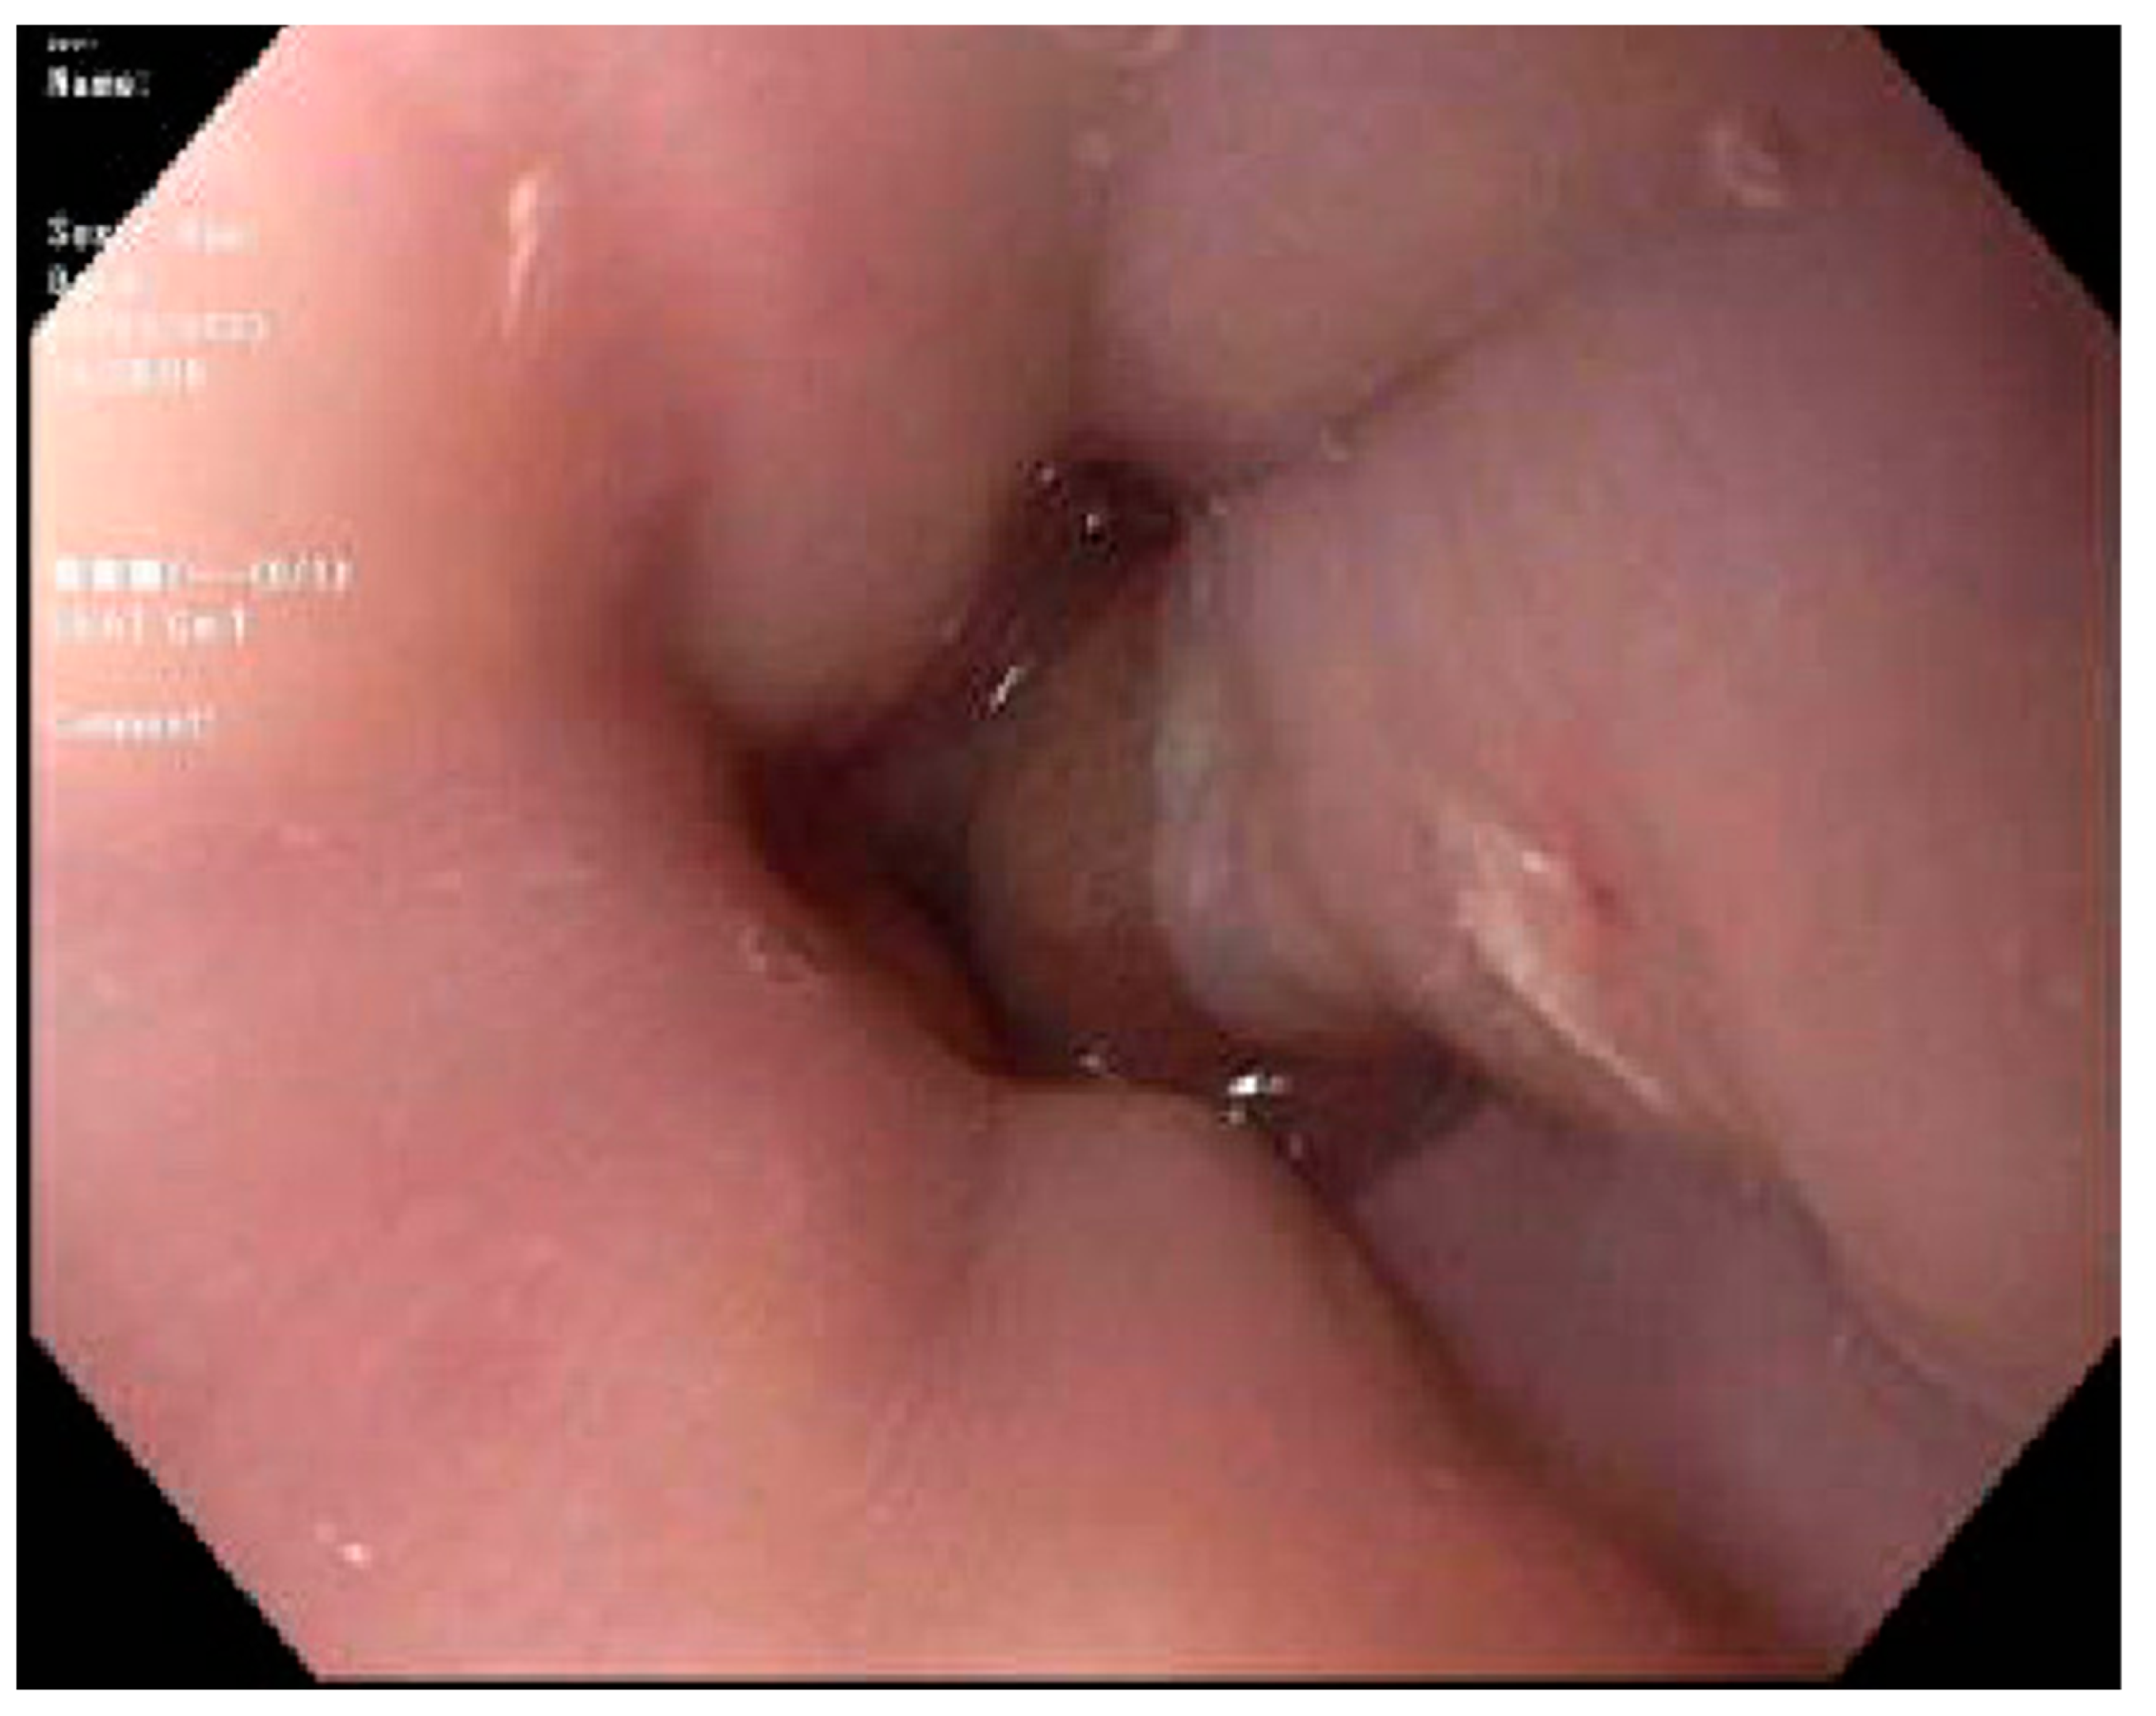

- Cruz-Correa, M.; Poonawala, A.; Abraham, S.C.; Wu, T.T.; Zahurak, M.; Vogelsang, G.; Kalloo, A.N.; Lee, L.A. Endoscopic findings predict the histologic diagnosis in gastrointestinal graft-versus-host disease. Endoscopy 2002, 34, 808–813. [Google Scholar] [CrossRef]